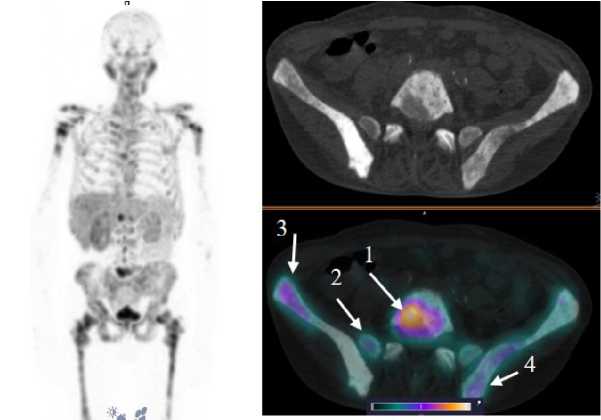

Рис. 4. MIP-реконструкция, КТ и совмещенное ОФЭКТ/КТ изображение больного кастрат-резистентным раком предстательной железы с множественными метастазами в кости через 2 ч после инъекции [99mTc]Tc-HYNIC-PSMA. На ОФЭКТ-КТ-изображении стрелкой отмечено накопление РФЛП в патологических очагах: L5 (1) SUVmax 22,8; боковые массы крестца справа (2) SUVmax 9,7; подвздошная кость справа (3) SUVmax 13,4; подвздошная кость слева (4) SUVmax 10,4

Fig. 4. MIP reconstruction, CT and SPECT/CT image of a patient with castrate-resistant prostate cancer with multiple bone metastases 2 hours after injection of [99mTc]Tc-HYNIC-PSMA. Accumulation of radiopharmaceutical in the pathological areas is indicated by the arrow on the SPECT-CT image: L5 (1) SUVmax 22.8; lateral masses of the sacrum on the right (2) SUVmax 9.7; ilium on the right (3) SUVmax 13.4; ilium on the left (4) SUVmax 10.4